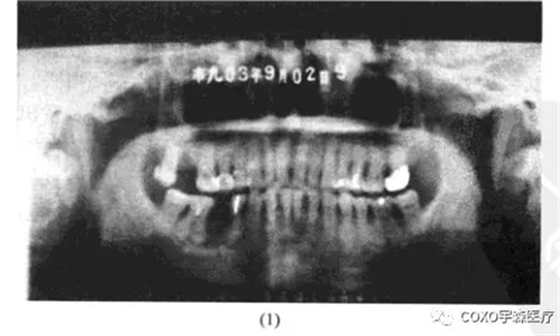

三、根尖周病與夜磨牙癥

病例 女性,20歲,因下前牙酸痛感,醫(yī)師為其攝片檢查示:1-1根尖區(qū)有透射陰影,范圍大不規(guī)則,認(rèn)為根尖區(qū)有病變,誤將1]開(kāi)髓,發(fā)現(xiàn)為活髓,暫封,未預(yù)約處理,半年后再攝片檢查1],發(fā)現(xiàn)1]牙內(nèi)吸收,并導(dǎo)致牙根穿孔,而T一直存在活力,仔細(xì)詢問(wèn)病史,患者有夜磨牙癥病史(圖13-6)

分析與評(píng)述

根尖周陰影,多數(shù)情況牙髓都已壞死,但是在確診之前,常規(guī)的牙髓活力測(cè)定是必需的。該牙無(wú)齲,無(wú)楔狀缺損,引起根尖區(qū)骨質(zhì)稀疏,尤其是下頜前牙,由于垂直方向受力,容易考慮到是咬合創(chuàng)傷,甚至是夜磨牙癥。雖然在處理的當(dāng)時(shí)1]還是活髓,最終仍有可能逆行性牙髓壞死。醫(yī)師未仔細(xì)詢問(wèn)病史、作牙髓活力測(cè)定,就開(kāi)髓,是工作不細(xì)致、不嚴(yán)謹(jǐn)、責(zé)任心不強(qiáng)的表現(xiàn)。

根尖周骨質(zhì)稀疏,又系活髓,應(yīng)詢問(wèn)有無(wú)外傷史,夜磨牙病史,當(dāng)證癥,如能查出引起夜磨牙癥之病因,應(yīng)當(dāng)去除致病因素,并用給板再調(diào)給磨對(duì)根尖有病變的牙行根管治療術(shù)。四、根尖周病與腫瘤及類(lèi)腫瘤疾病